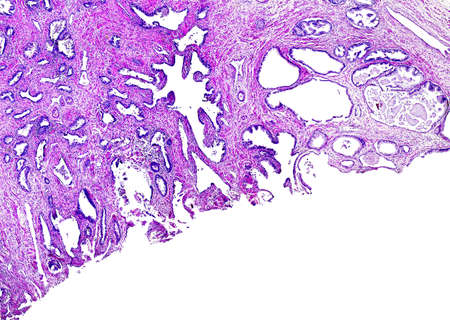

Large-bowel adenocarcinoma. Cancer cells arranged in cords or strands with empty central spaces remembering the normal crypts of the colon mucosa.